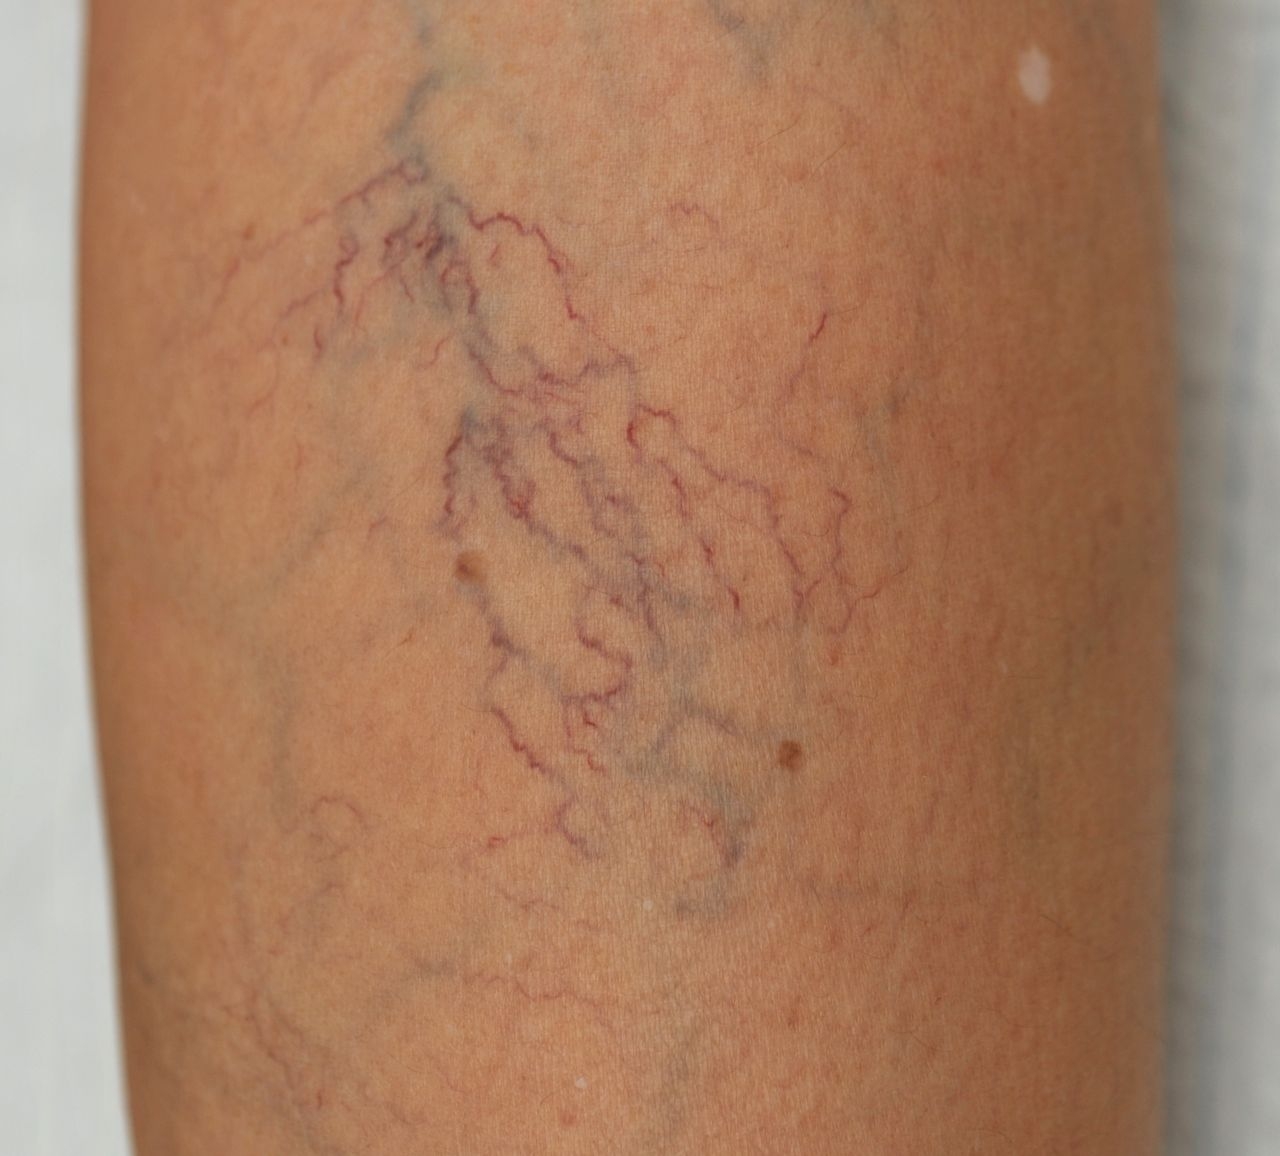

تفاوت بین رگهای عنکبوتی و رگهای واریسی

رگ های واریسی - واریس

اغلب مردم این دو اصطلاح را به یک معنا بهکار میبرند، ولی این دو ناراحتی پوستی، کاملا از هم متمایزند. دلیل ابتلا به آنها شاید یکسان باشد، ولی شکل ظاهریشان با یکدیگر فرق دارد.

رگهای عنکبوتی، که به آن مویرگ فراخی نیز میگویند، برروی پوست بهصورت خطوط نازک یا شبکهمانند ظاهر میشوند. برخی هم به این رگها اصطلاحا خوشههای ستارهفشان می گویند؛ زیرا ظاهرشان شبیه نقطههای کدری است که همگی در یک نقطه از سطح پوست متمرکز شدهاند. این ساختار بیشباهت به خوشههای ستارهای درون کهکشانها نیست.

رگهای عنکبوتی همانند رگهای واریسی مناطقی از قبیل پا، پشت ران، ماهیچه ساق پا، قوزک و از مچ به پایین را درگیر میکنند. این رگها از واریس کوچکترند و ازآنجاییکه برروی لایههای سطحی پوست قرار دارند، درد و علائم حادی از خود نشان نمیدهند. رگهای مشبک هم ناهنجاری وریدی دیگری است که اندازهی رگ در آن بزرگتر از رگهای عنکبوتی و کوچکتر از رگهای وریدی است.